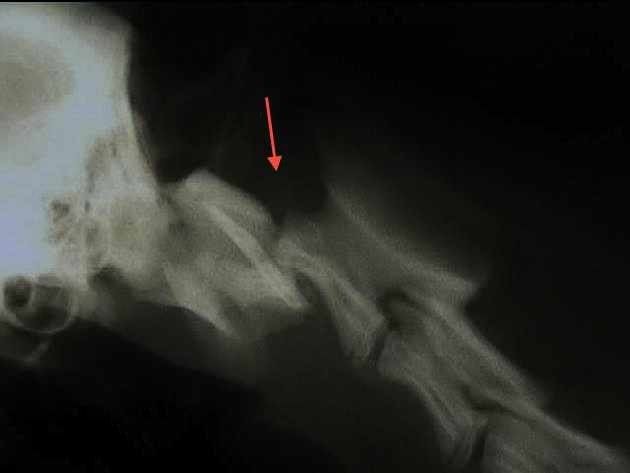

X-ray of limbs:

For the search for fractures but also the evaluation of various joint problems such as osteoarthritis or dysplasia.

Evolution of an odo-femoral dysplasia in osteoarthritis after a few years